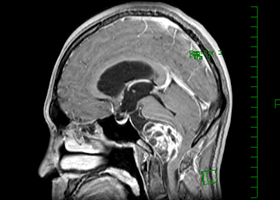

症例3)31歳男性、延髄前面巨大舌下神経鞘腫

[画像所見]

-

嚥下困難、四肢麻痺で発症しました。 -

術前 -

術後 -

術後、患者さんは元気に自宅退院されました。